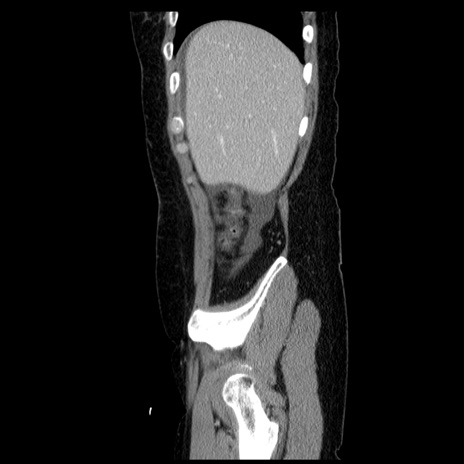

症例6(矢状断像)

【症例】50歳代女性

【主訴】下腹部痛

【現病歴】本日朝より下痢2回あり。 昼食を食べた後、嘔吐3回、下腹部痛認め、症状軽快せず、当院救急搬送。

最終食事:本日昼(生ものなし)。 昨日の夜、刺身を食ぺたとのこと。周囲に同様の症状の者なし。普段、排便は毎日あるとのこと。

【既往歴】卵巣癌術後(8年前に当院で卵巣摘出)

【身体所見】 意識清明、腹部:平坦、腸蠕動音→、やや硬、下腹部自発痛・圧痛あり、反跳痛あり、筋性防御なし。

【データ】WBC 16000、CRP 0.01